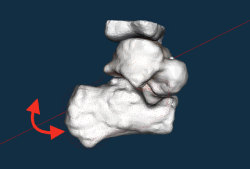

Figura 5. Representación gráfica del procesamiento de las imágenes en carga y posiciones extremas (calcáneo en gris representa la posición en inversión; nube de puntos rojos representa la eversión). Nótese la representación del eje helicoidal a través del cual el calcáneo rota y se traslada (flecha roja).

En nuestra experiencia, tras el análisis de una serie de 72 pies y tobillos estudiados mediante la TC dinámica en carga simulada tanto en voluntarios sanos como en pacientes afectos de inestabilidad crónica de tobillo, se observó que existen diferencias significativas en el rango de movilidad rotacional a través de un eje helicoidal trazado en la articulación subastragalina a partir de las posiciones extremas en inversión y eversión subtalar (Figura 4). Manteniendo el astrágalo fijo en la mortaja tibioperonea con una dorsiflexión mantenida de 10°, el calcáneo viró en mayor grado a través de un eje helicoidal en los tobillos sintomáticos cuando se compararon con el tobillo contralateral asintomático (Figura 5). Asimismo, se observó una correlación entre variables de descobertura articular en la articulación subastragalina y calcaneocuboidea en las posiciones de máxima inversión del retropié y rotación interna (Figura 6).